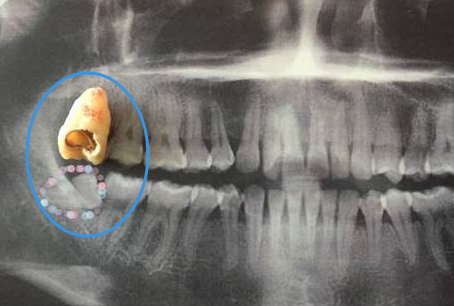

1、一顆智齒拔除的價(jia) 格通常在數百元到兩(liang) 三千元不等,主要是因為(wei) 拔牙難度不同。比如說沒有萌出的智齒相對萌出的智齒拔牙要簡單一些,費用也低一些,因此,具體(ti) 的價(jia) 格是由專(zhuan) 業(ye) 拔牙醫生來衡量的。

4、如果隻拔牙一顆的話,可能費用會(hui) 貴一些,如果山下牙同側(ce) 一起拔牙,可能會(hui) 相對便宜一些。因為(wei) 上牙智齒拔牙比較簡單,費用比較低,但是下牙智齒拔牙難度高,費用貴。